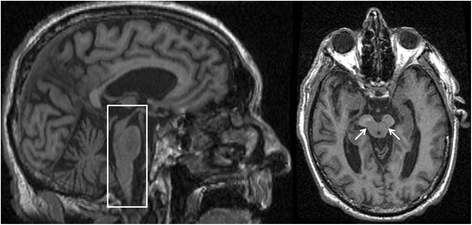

View Psp Brain Disease Pictures. Psp is one of the tauopathies which also includes corticobasal degeneration, picks disease, frontotemporal pathologically, gross examination of the brain in psp shows midbrain atrophy. Progressive supranuclear palsy (psp) is a rare brain disorder frequently confused with parkinson's disease.

Psp affects your ability to walk progressive supranuclear palsy is rare. Brain support network continually reviews most of the resources available on psp. It causes problems with walking, balance, eyesight, behavior, swallowing and emotions. Learn about different brain diseases, as well as the causes, symptoms and treatment options, at u.s.